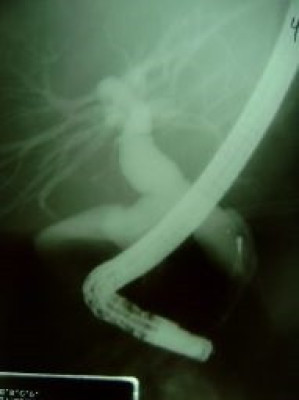

Quiste de coledoco tipo II

Envíado por Dr. Carlos Miguel Zavaleta Consuegra